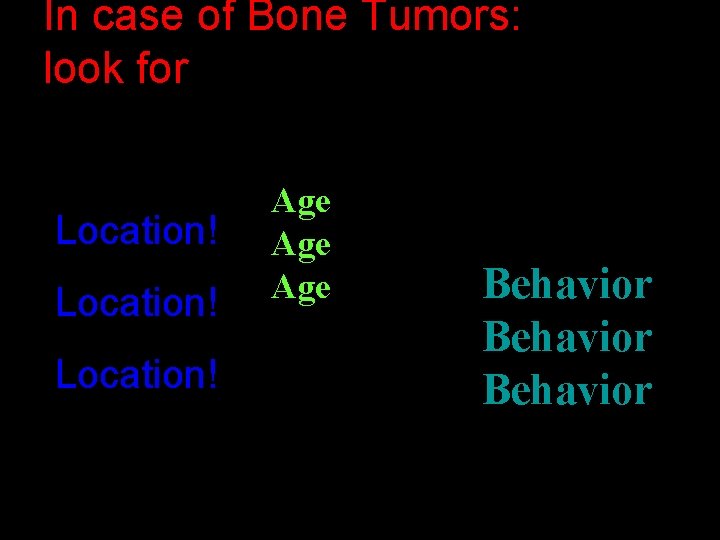

In case of Bone Tumors: look for Location! Age Age Behavior

Location and age of patient most important • parameters in classifying a primary bone tumor. Simple to determine from plain • radiographs.